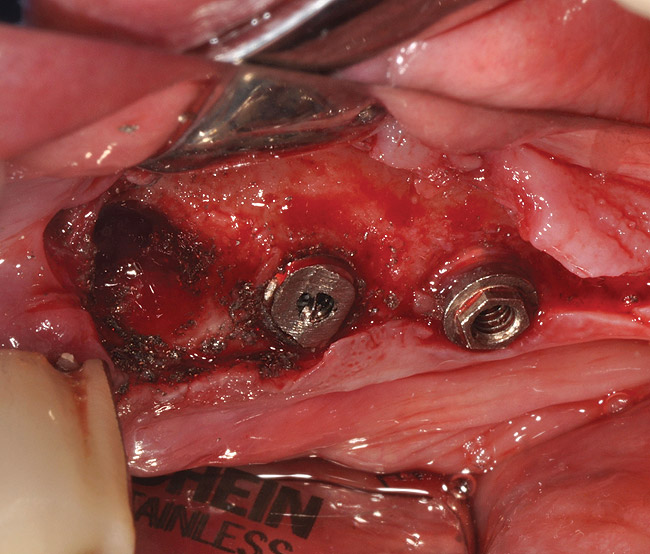

There are several sizes of trephines available that correspond to various implant diameters (Figure 8, Figure 9, Figure 10 and Figure 11). The smallest effective size trephine should be selected to avoid collateral damage to the neighboring bone, teeth, and/or implants. The internal diameter of the trephine needs to be slightly larger than the implant to avoid engaging the implant body. The preferred speed to use a trephine is 1,200 rpm to 1,500 rpm with copious irrigation. This technique is one of the most invasive options for implant removal. Fatigue fracture of the mandible after the use of a trephine bur has been reported.25 Osteomyelitis is another complication that may occur following explantation with a trephine bur, particularly if bone is overheated.26 Thus, trephine burs are only indicated when absolutely necessary, and the retrieval procedure should be carefully planned and performed under copious irrigation with cooled saline.26 As previously stated, if the crown and abutments are present, it is essential that they are cut off and/or removed prior to trephine use. This allows for use of the smallest diameter trephine (Figure 9, Figure 10 and Figure 11). Oftentimes only the coronal half of bone around the implant needs to be removed to loosen the implant, at which point elevators, forceps, and, where possible, torque drivers may be employed as part of a combination technique, as described in the following section.

Figure 8  Trephine bur used to remove bone around the implant.

Figure 9: Sufficient bone has been removed (left implant) by using the trephine bur; implant platform (middle implant) is to be cut.

Figure 10  Implant removed with forceps.

Figure 11  Remaining implant after cutting implant platform to allow for use of the smallest diameter trephine.

Figure 12  Trephine bur used to remove bone around the failed implant guided by the implant mount.

Figure 13  Combination technique with the counter-torque ratchet used following bone removal with the trephine bur.